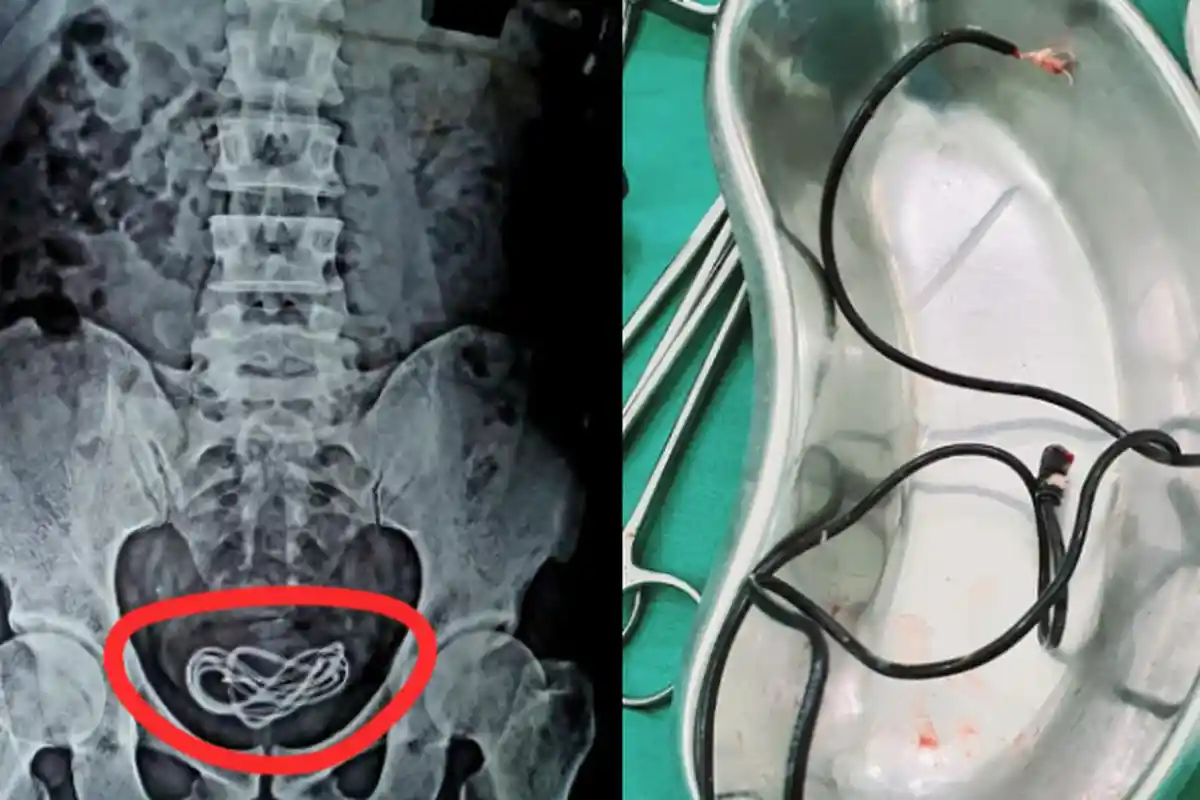

Tim dokter di India berhasil mengangkat kabel cahrger yang memiliki panjang hampir dua kaki (50 cm) dari kandung kemih pria berusia 30 tahun itu.

Melansir dari CTV News, Senin (8/6/2020), Tim dokter di India berhasil mengangkat kabel charger yang memiliki panjang hampir dua kaki (50 cm) dari kandung kemih pria yang berusia 30 tahun itu.

"Saya mengoperasi dia (pasien) dan tidak menemukan apa pun di saluran pencernaannya, tetapi malah menemukan kabel charger ponsel di kandung kemihnya,” kata Islam.

“Kalian semua pasti sudah menebak titik masuk dan rutenya (masuk melalui uretra penisnya ke kandung kemihnya),"sambungnya.

X-ray mengkonfirmasi bahwa kabel itu dimasukkan melalui uretra penis.